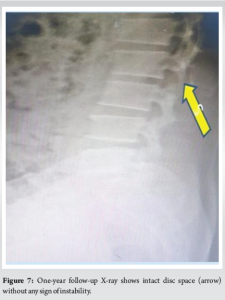

The post-operative period was uneventful. During the post-operative period, there was significant improvement in motor power and bowel and bladder control. The patient was mobilized from day 01 with support. With one year follow-up, the patient is pain-free and has returned to his routine activities. Fig. 7 shows the follow-up x-ray of the patient without any sign of instability.